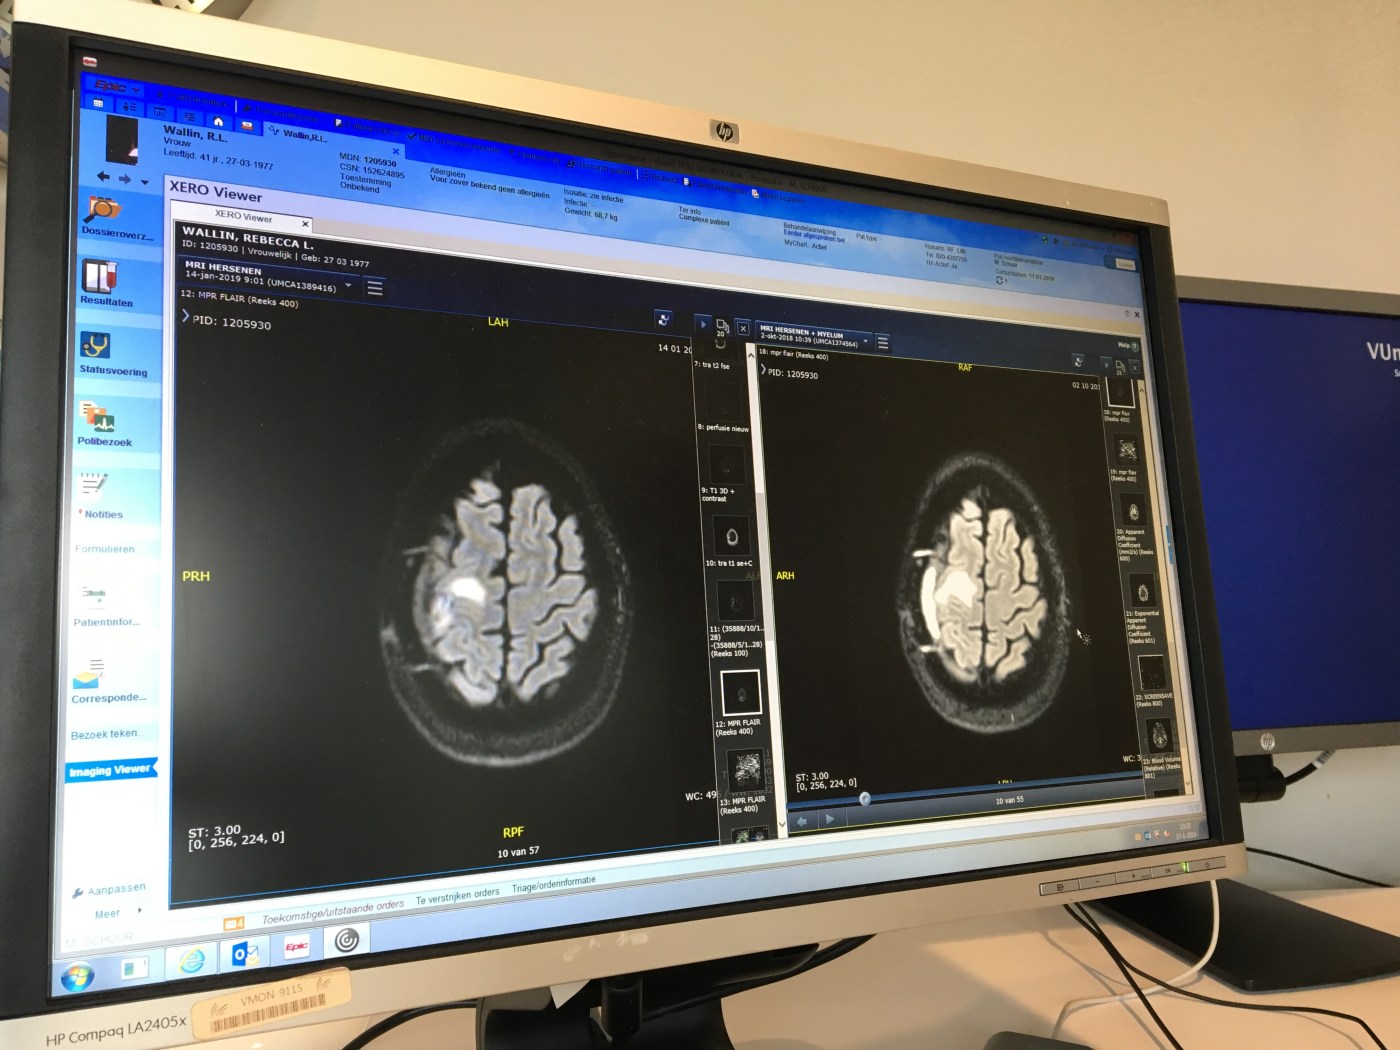

That was week 1. Moving on to week 2; despite having to get to the VU by 08:30 (my body no longer recognises this time of day), despite getting on the ‘direct’ tram (only to find it was on a detour route past the Olympic Stadium), and despite not then having time to grab a coffee before my MRI, I still rock up to hospital on 14th January with a spring in my step.

Having completed the MRI scan and made my way home, I then had a week to wait before seeing my Neurologist for the results. However, the following day I got a routine notification to tell me my medical file had been updated and my results were now available in my dossier online.

Well of course I looked, wouldn’t you? I know the results need explanation and context, and I know they’re in Dutch, but I still had to look.

Of course, I immediately wished I hadn’t, as my Google Chrome browser automatically tried to translate the Dutch report into English. Seeing phrases like “Question: Residual edema? Possible new lesions?” I started to think (always dangerous with Dr Google), and the excitement of being on the home straight suddenly evaporated. If I had more edema or lesions in my head, the last thing they should do is knock out my immune system with more chemo, they’ll be wanting to get me back into neurosurgery…

I emailed my Neurologist and asked for Monday’s appointment to be brought forward. It was, and I saw Dr Schuur on Thursday instead.

The results are good

So it turns out Google’s translation was correct, but the ‘question’ was not a concern from the new scan; but an outstanding question from the old scan, which my Neurologist was asking the Radiologist to rule out. Which he did.

So my Neurologist is happy that there are no new lesions, and the residual edema is to be expected and nothing to be concerned about. She did a physical examination (the usual tests of strength and coordination) and finished off by saying I’m better than when she last saw me, the scan looks good, and she’s happy I’m fit to drive. Get in!